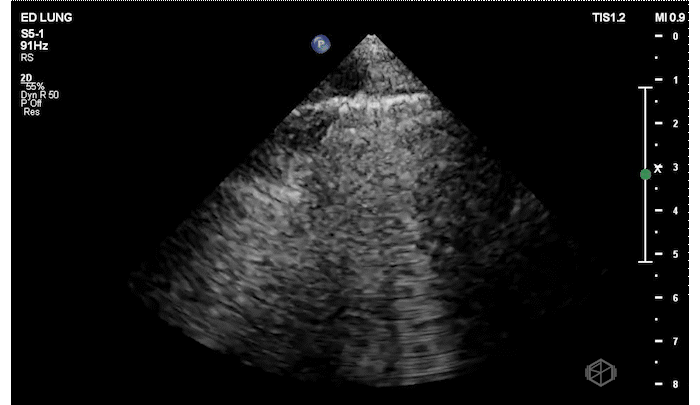

Before even the chest x-ray Dr. Mehta did a lung ultrasound (LUS) that demonstrated the following:

The patient has focal B-lines on the right side with diminished lung sliding. The presence of B-lines rules out pneumothorax. The right lung base has at least a moderate sized complex pleural effusion with septations.

Diagnosis: Complex pleural effusion, empyema

CT scan performed a day later demonstrated: “complex moderately-sized verging on large right pleural effusion which is an empyema, with associated atelectasis/pneumonia of the right lower lobe,” which we already knew and the patient had a pig tail placed that put out purulent material.